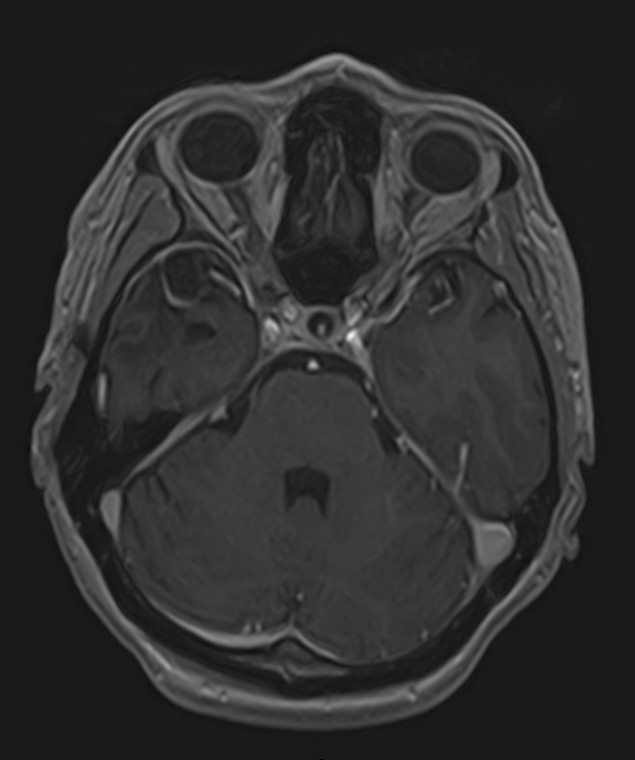

МРТ головного мозга с контрастированием – методика проведения магнитно-резонансной томографии, при которой внутривенно вводится препарат, содержащий гадодиамид (соли металла гадолиния). Контрастное вещество не проникает через гемато-энцефалический барьер и в норме не накапливается в тканях головного мозга. Однако при нарушении его целостности способно накапливаться в патологических очагах, в частности, в опухолях, зонах воспаления и участках демиелинизации нервных волокон.

Это способствует ранней диагностике заболеваний головного мозга, таких как рассеянный склероз, доброкачественные и злокачественные новообразования. Кроме того, с помощью контраста можно оценить степень и характер васкуляризации патологического процесса.

Исследование в нашей клинике выполняется на современном высокопольном томографе экспертного класса TOSHIBA VANTAGE TITAN 1,5 Тесла, который использует разные режимы сканирования с толщиной среза от 1мм в различных плоскостях с последующей цифровой обработкой полученных данных для создания трехмерных изображений. Аппарат позволяет выявлять структурные изменения в веществе головного мозга уже на начальной стадии, когда другие методы не дают результатов.